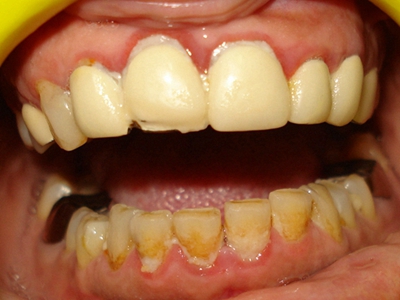

牙龈炎常见的病因是口腔卫生差,不良的口腔卫生使牙菌斑沉积于牙齿与牙龈之间,造成龈沟加深,另外牙结石、不良修复体等也可造成牙龈炎的发生。

牙龈炎患者可通过改善口腔卫生控制疾病,同时使用抗菌漱口液,如复方氯己定含漱液,并进行彻底的洁治处理。必要时,重新修整修复体的不良外形,并祛除局部刺激因素。